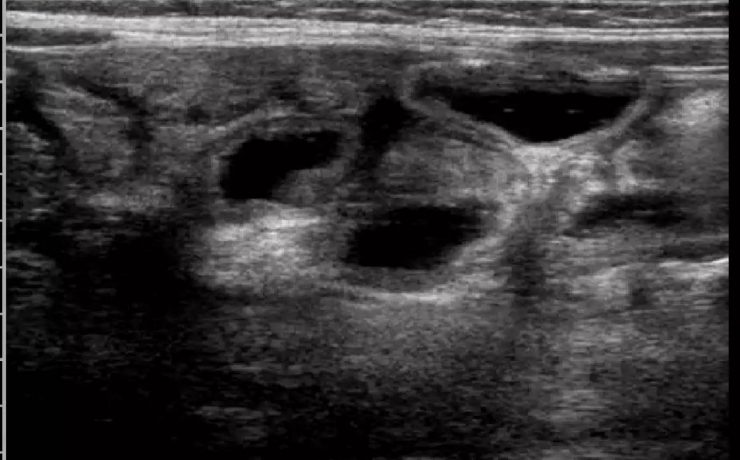

Existen alteraciones ováricas valorables por ecografía tratándose generalmente de alteraciones foliculares las cuales se presentan clínicamente como defectos en la maduración además del número de los mismos. Ecográficamente se diferencia el tamaño, el grosor capsular y su estroma puede estar aumentado e hiperecogénico. Otra patología son los quistes que